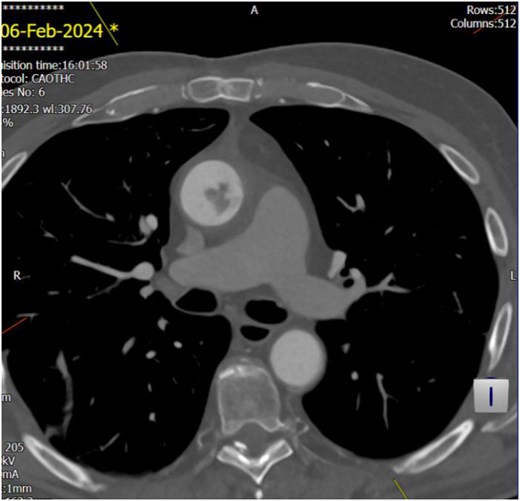

The echocardiogram showed no valve vegetation or mural thrombus. However, CT angiography of the thoracic aorta (Figs 3 and 4) revealed focal ulceration in the ascending aorta (1.3 cm) with an associated intraluminal filling defect (3.5 cm), appearing unstable. Additional small ulcerations and soft tissue were cuffing around the ascending aorta, with anterior mediastinal stranding suggestive of aortitis.

Unstable focal ulceration (1.3 cm) with a 3.5 cm intraluminal filling defect in the ascending aorta. Additional small ulcerations and periaortic soft tissue cuffing are present, along with anterior mediastinal stranding indicative of aortitis.